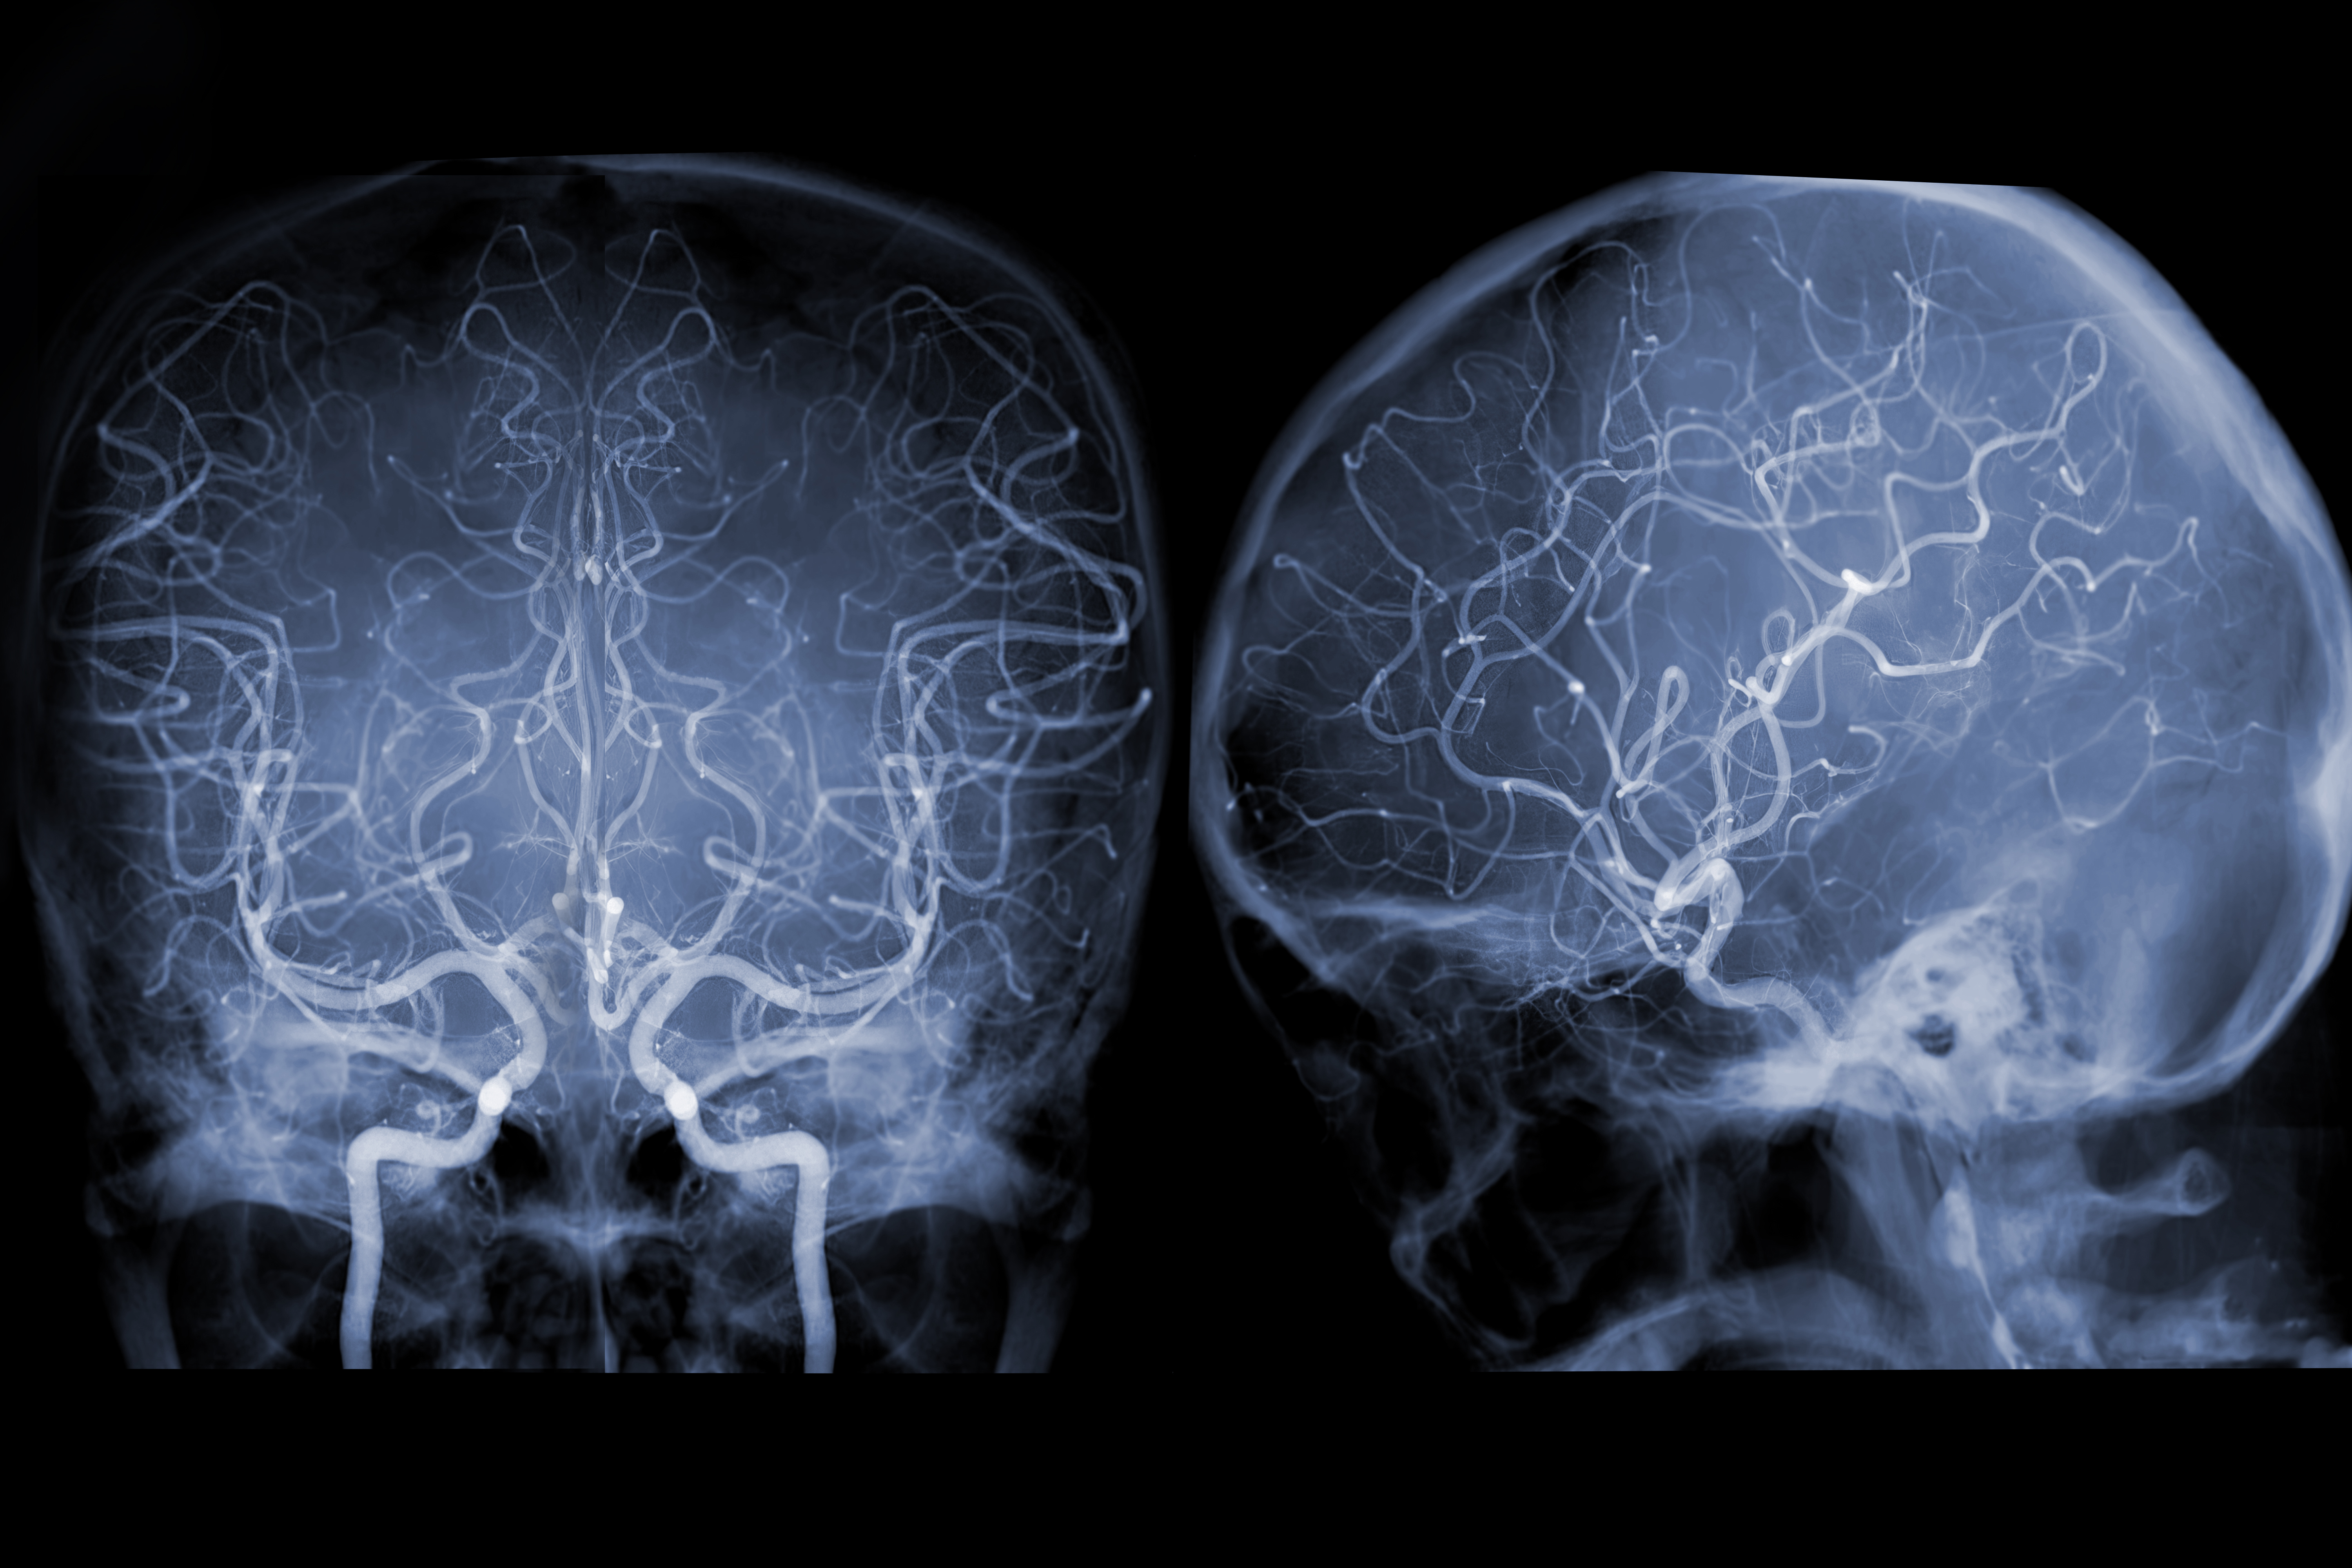

间脑镜头下的x光片

在进行脑部ct检查时发现脑部高密度影.有患者怀疑是不是得脑肿瘤